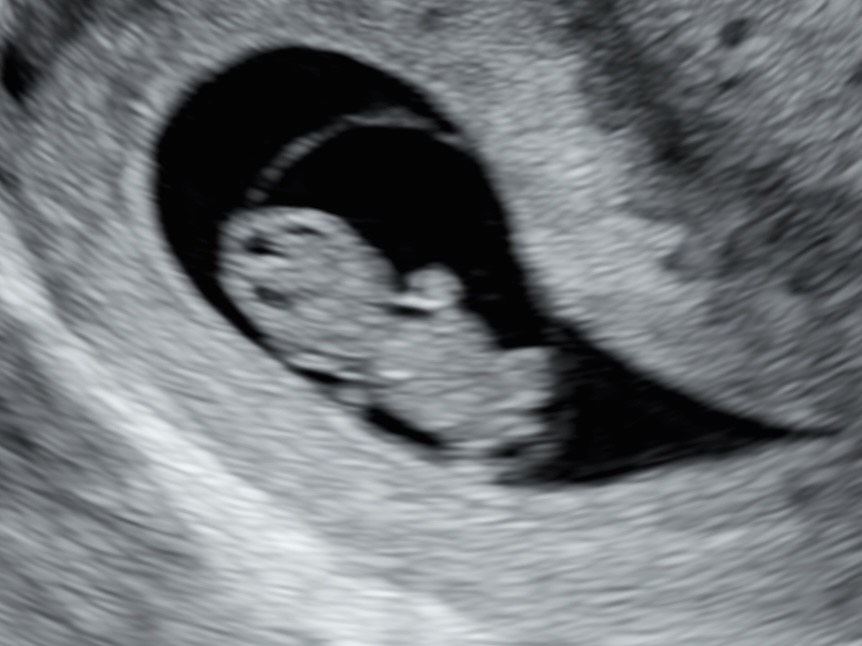

Tähän ultraääneen voit tulla missä raskauden vaiheessa tahansa käytyäsi ensimmäisessä julkisessa ultraäänessä eli rv 12+0 jälkeen. Käynnillä tarkastellaan vauvan liikkeitä, kuunnellaan sydänääniä, otetaan mittoja painoarviota varten ja ihan vaan ihaillaan vauvaa.

Joku kaipaa ehkä varmistusta vauvan hyvinvoinnille ennen liikkeiden tuntemista, toinen haluaa kurkistaa vauvan sukupuolta (onnistuu parhaiten kun raskausviikkoja on 16+0 tai yli), kolmas ei ehkä tunne raskautta vielä omakseen ja kaipaa jotain konkreettista kontaktia pieneen. Joka tapauksessa tutkimuksessa pyritään aina varmistamaan se, että vauva voi hyvin.

Sairaalassa tehtävässä rakenneseulassa käy joskus niin, että sukupuoli jääkin näkymättä, vaikka sen olisi odottanut kuulevansa. Olisi hyvä sinnitellä kaksi viikkoa ennen seuraavaa ultraa, jotta vauvasta ottamamme painoarvio ja hänen vointinsa varmistaminen olisi järkevää.

Mukaan saa kuvia tulostettuna ja sähköisessä muodossa. Hinnoittelun muuttumisen vuoksi tämä käynti ei sisällä 3D/4D kuvia.